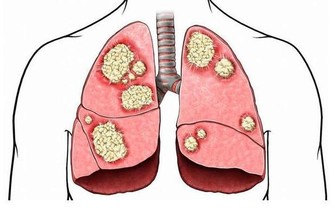

如果癌症擴散到前列腺外,會出現其他症狀。這些症狀包括:

5. 其他癌症,患有膀胱癌、肺癌或甲狀腺癌的患者,出現前列腺癌的風險較高。